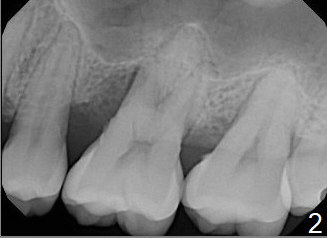

A 41-year-old man has had severe periodontitis at #14 for the last 11 years (Fig.1-3). Finally the tooth is mobile. Draw blood for PRF membrane (x4). After use of Magic Drill with 3 mm stopper, tap Magic Lifter for sinus lift. Insert 1-2 PRF membrane(s) and Vanilla graft prior to further osteotomy with UF drills until 4.5 or 5 mm. Insert tap drill for primary stability. If it fails, switch to IBS dummy implants.

2